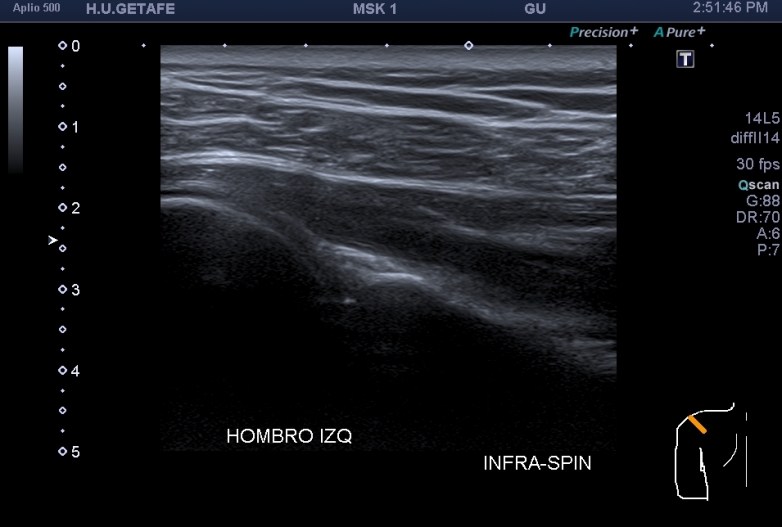

4.Tendón del infraespinoso

En el final del protocolo tenemos el infraespinoso. En relación con este corte te voy a contar que es un corte donde estudiamos en normalidad, articulación glenohumeral, labrum posterior (triangular e hiperecogénico), músculo infraespinoso como puedes ver en las dos imágenes siguientes, donde existe normalidad en la primera y donde coexiste la anatomía con la patología por la ausencia del labrum, sustituido por una buena cantidad de líquido justo en la articulación glenohumeral.